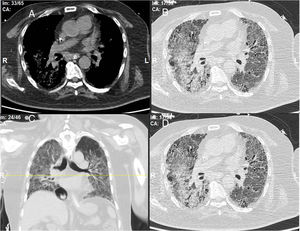

The chest consultant considered lung affection to be related to MTX toxicity and the drug was discontinued and patient shifted to oral Azathioprine (AZA) in a dose of 150mg/day and prednisolone was increased to 15mg/day/po; he continued the same dose of HCQ. Shortly after the patient started to develop intense myalgia of both thigh muscles with no clinical evidence of motor weakness and the creatine kinase (CK) levels were within normal range. He had no Raynaud's phenomenon and no signs of gastroesophageal reflux. After 1 week, the chest symptoms worsened and the patient was admitted to the intensive care unit with severe respiratory distress. Oxygen saturation was 78% on room air and follow-up high-resolution CT (HRCT) of the lungs showed extensive areas of ground glass veiling and opacification together with interstitial subpleural infiltrates (Fig. 2). The patient was transferred to the ICU with acute respiratory failure due to exacerbation of interstitial autoimmune pneumonitis and urgent mechanical ventilation was carried out together with IV pulse steroids, IV antibiotics, and other supportive measures. During the ICU admission, the patient improved clinically and the mechanical ventilation could be discontinued; after 1 month, he was discharged on long-term oxygen therapy (2L/min), high-dose oral steroids (40mg/day/po), and oral AZA (150mg/day).